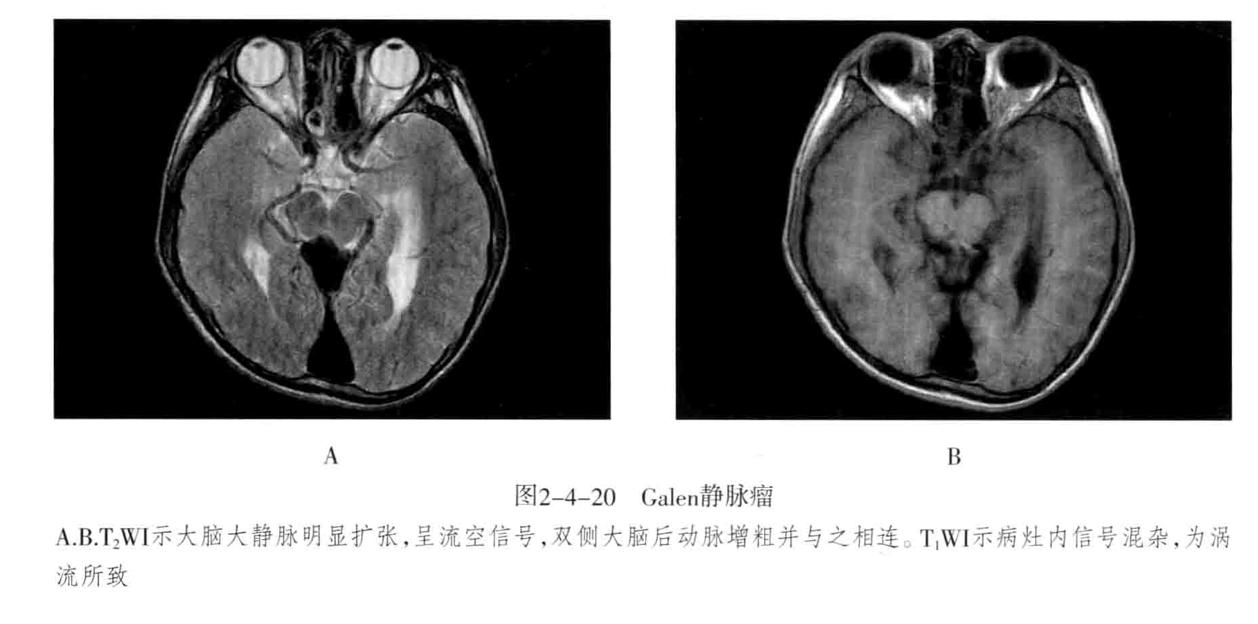

Galen静脉瘤是由于动-静脉短路,大量血流进入大脑大静脉,造成该静脉瘤样扩张所致。多见于儿童,特别是婴幼儿。典型的Galen静脉瘤包括明显扩张的Galen静脉和扩大迂曲的引流静脉。因动静脉短路造成盗血现象,可引起相应区域脑缺血。

Galen发生于Galen静脉区的特定部位,较大的Galen静脉瘤压迫中脑,导致中脑导水管闭塞,引发梗阻性脑积水。

脑血管造影、MRV/A:可直接显示扩张的瘤体,同时可见扩张的颈动脉或椎动脉分支直接与Galen静脉短路。CTA可见扩张的瘤体、供血动脉、引流静脉及扩张的静脉窦。

CT平扫:大脑大静脉区可见边界清楚的类圆形、三角形的高密度影,密度均匀,边缘常可见点状线状钙化。可见三脑室及其以上脑室系统积水,增强后均匀强化,有时可显示增粗的供血动脉和引流静脉及扩张的静脉窦。

MRI表现:是确诊Galen静脉瘤最好的方法;大脑大静脉区边界清楚的类圆形或三角形的信号不均的病灶。增强呈血管样明显强化,血流瘀滞表现为T1WI等或低信号、T2WI稍高信号。